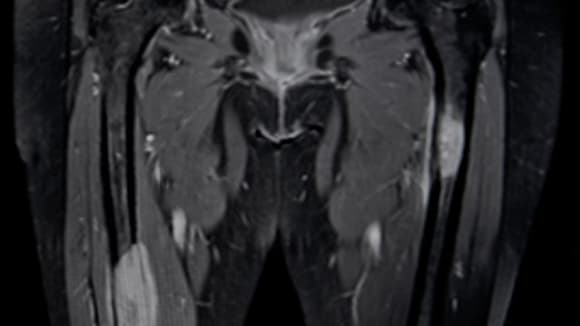

une IRM pelvienne ou une uro-IRM si l'uroscanner est contrindiqué;